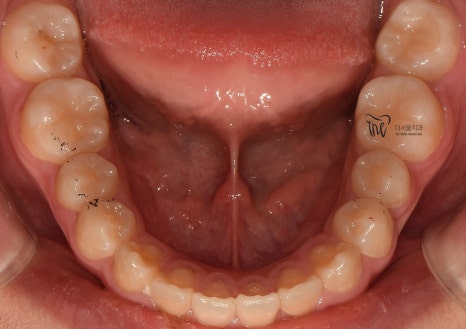

근데 또 교합면에서 보면, 악궁의 형태 자체는

그렇게 나쁜 편은 아닙니다. 다만, 회전이 되어있는

일부 치아들 및 치간이개의 현상 이외에는

별다른 특이사항을 볼 수 없죠.

교합면에서 봤을 때는, 거의 무턱 교정 치료가

다 끝난거와 같은 느낌을 받으실 수 있습니다.

원래, 악궁 자체는 그렇게 나쁜 편은

아니였기 때문에 크게 달라졌다고 느낌을

받기는 쉽지 않네요.